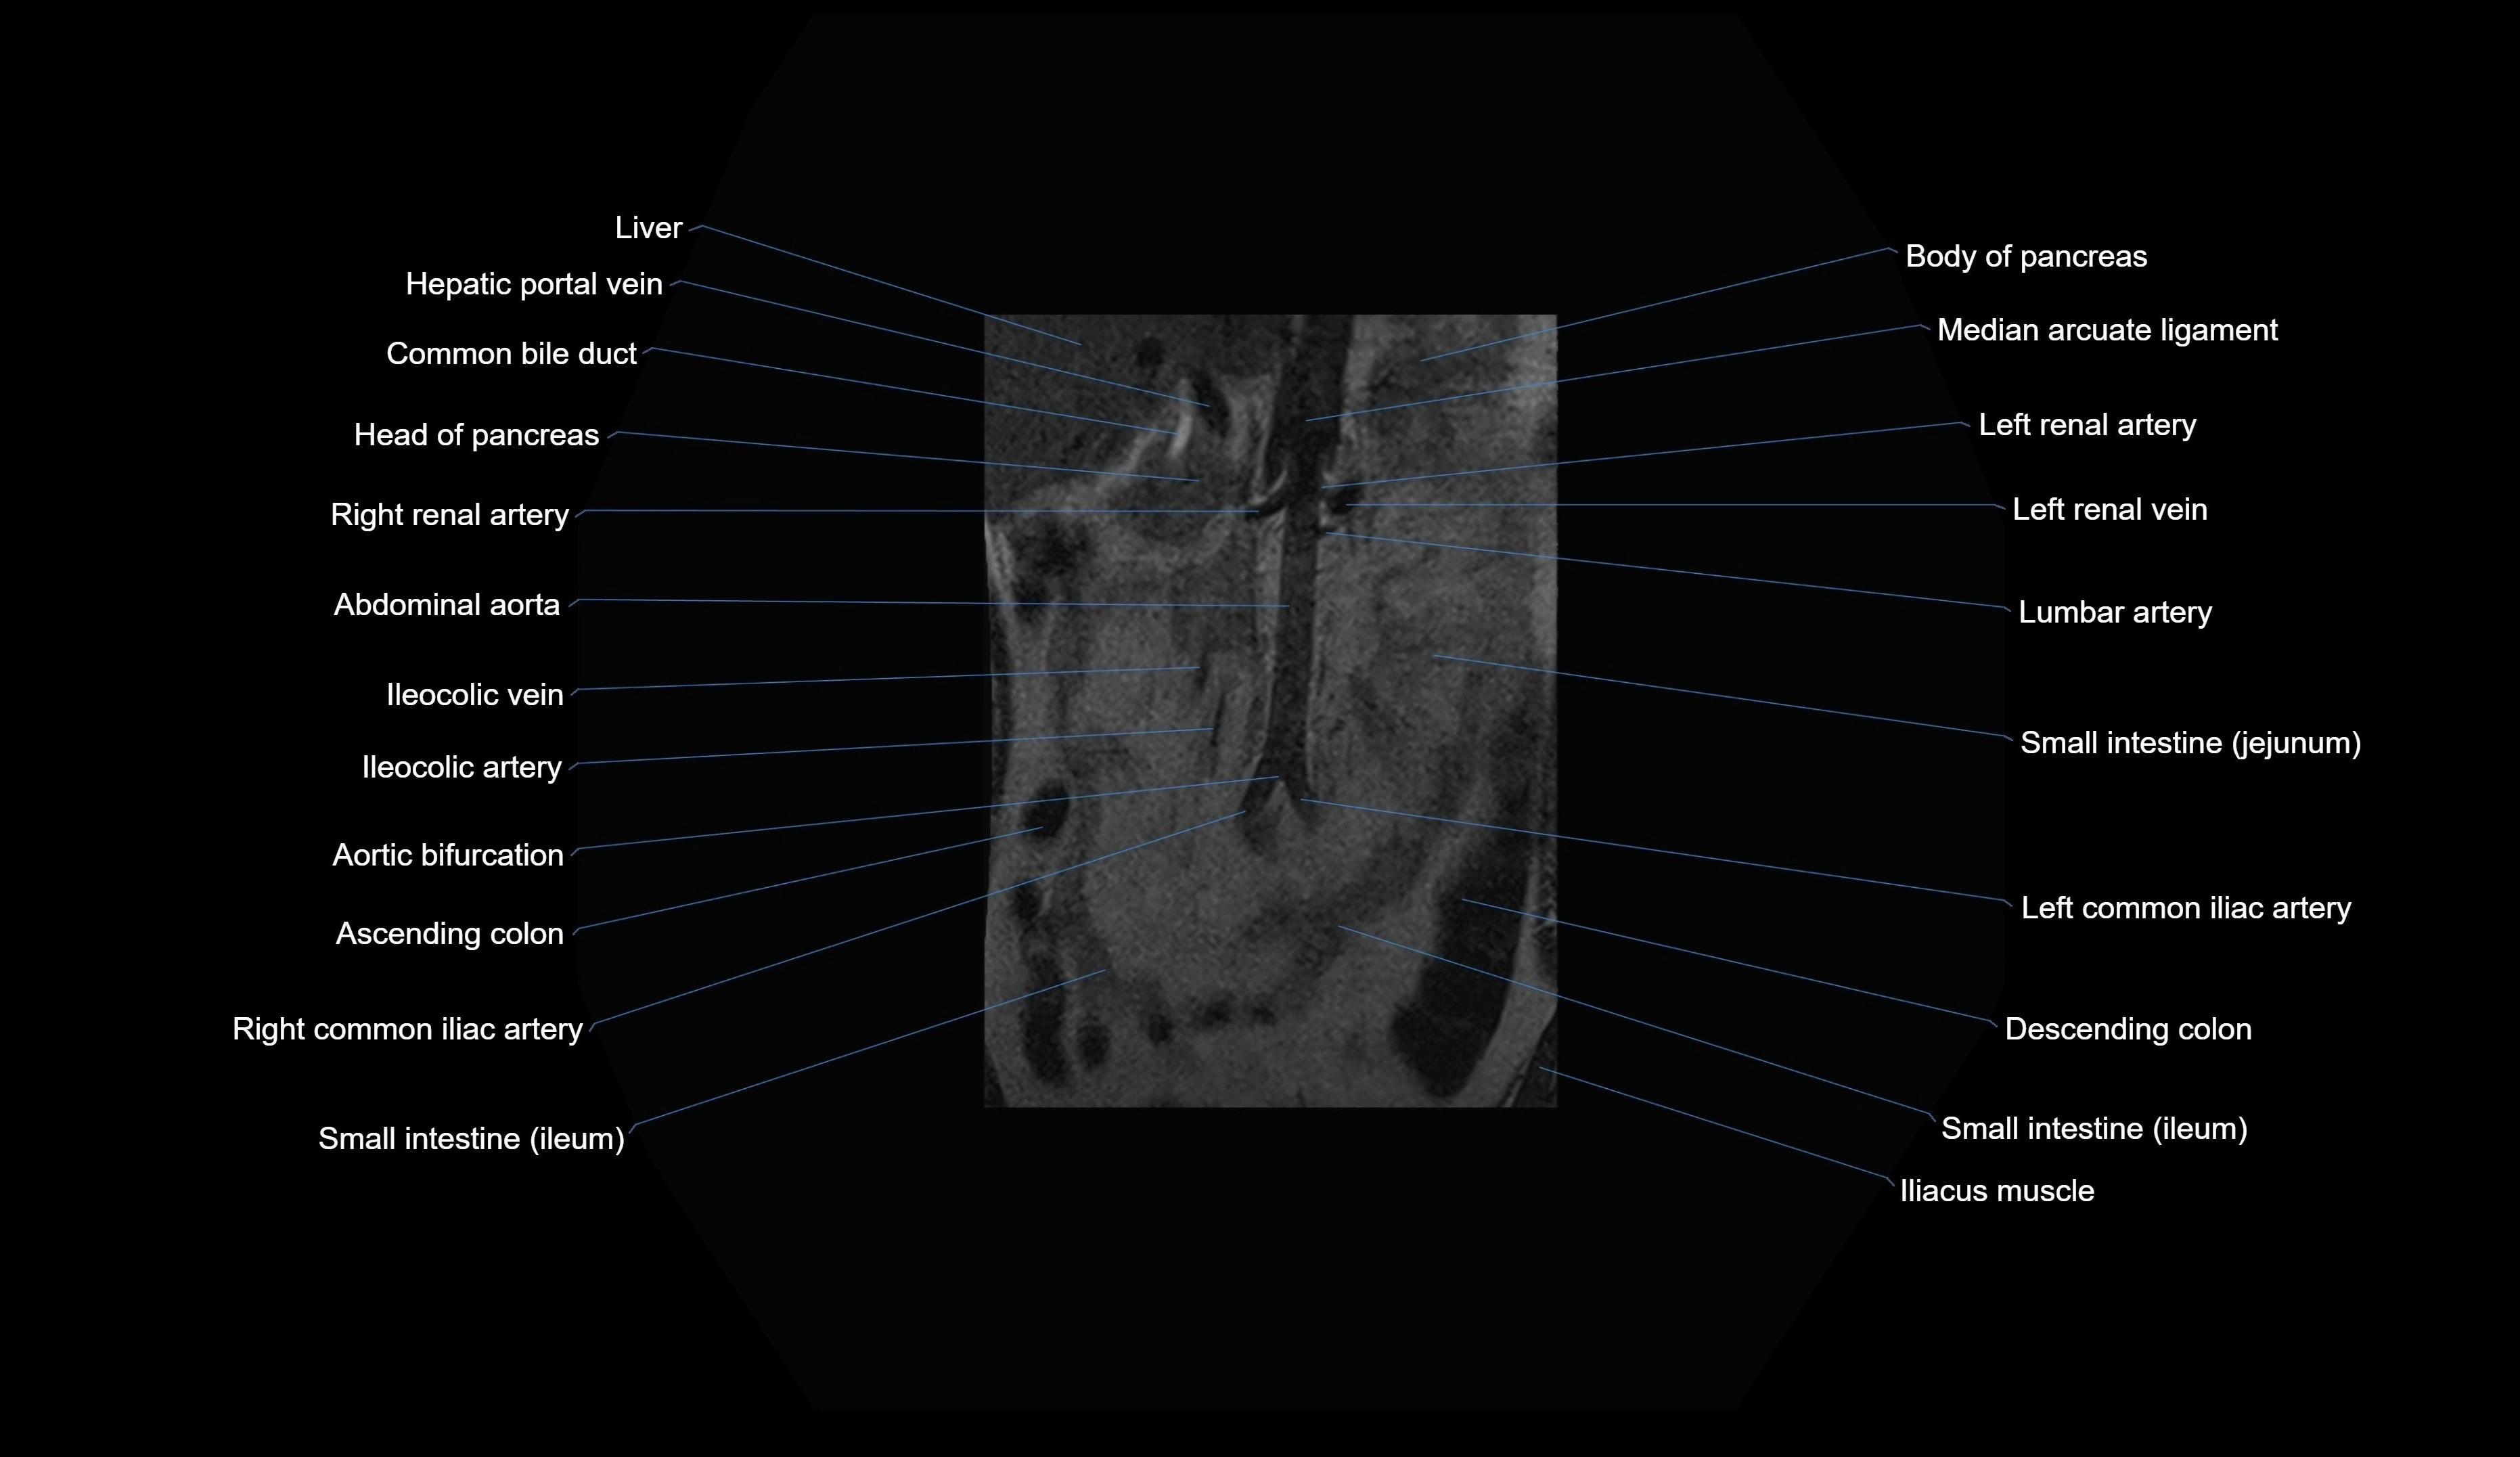

CT images